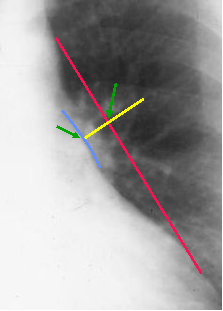

The distance

between the

tangent and

the main

pulmonary

artery (between

two small

green arrows)

falls in a range

between 0 mm

(touching the

tangent line) to

as much as 15

mm away from

the tangent line

If we draw a

tangent line

from the apex

of the left

ventricle to the

aortic knob

(red line) and

measure along

a

perpendicular

to that tangent

line (yellow

line)